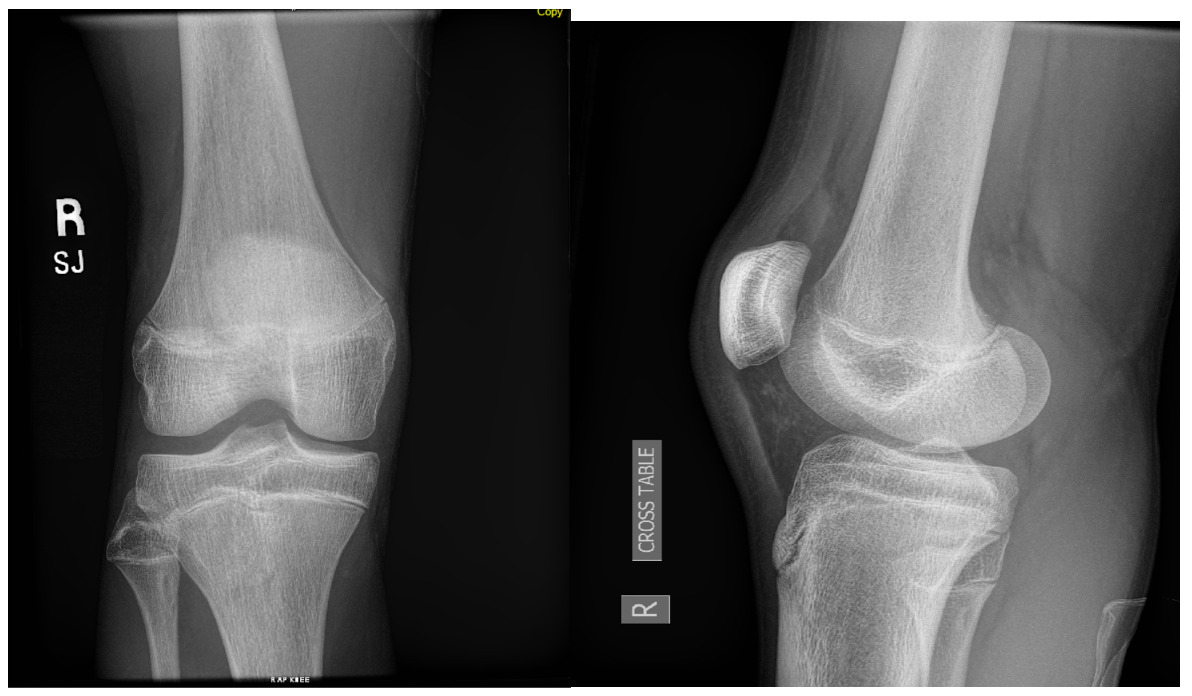

A 15-year-old male weighing 150 pounds and standing 6 ft 1 in tall, with no past medical history, presented to the clinic with buckling, catching and locking of the medial knee. He is a high school athlete who sustained a non-contact injury involving knee flexion combined with external rotation during a football game. He immediately reported a pop in the knee followed by stiffness and swelling. Clinical examination revealed joint effusion and medial and lateral joint line tenderness, on the inferior pole of the patella and tibial tubercle. Passive range of motion was limited, and both Lachman and McMurray tests were positive. Radiographs confirmed open physes with no evidence of fracture or malalignment., MRI demonstrated bony contusions and a substantial ligament injury, with a high-grade partial ACL tear, along with questions of peripheral posterior medial meniscus root tearing (Figures 1, 2). Management options were discussed with the patient, and he elected to proceed with surgical fixation. An additional consent was obtained from parental guidance for the possible publication of the surgical technique.